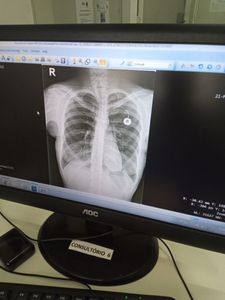

Artrite reumatóide idiopatica, lúpus, fibromialgia, espondilite anquilosante, síndrome anti fosfolipídios, fibrose pulmonar idiopática,doença de crhon e  DPOC,  já estou a 2 anos na fila do Sisreg mas não me chamam e por conta da pandemia não tem nem previsão de quando será marcado. Tenho todos exames e laudos para comprovar, se alguém quiser ver eu envio. Conto com sua ajuda, qualquer quantia já me ajuda.